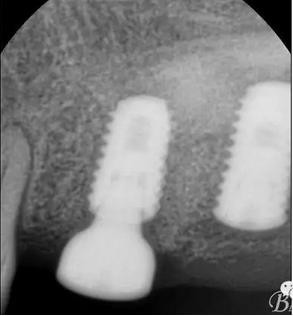

術(shù)后x光片,右上6直接上愈合基臺,但未完全就位,右下7手術(shù)過程略

這是術(shù)后1月的片子,重新就位愈合基臺